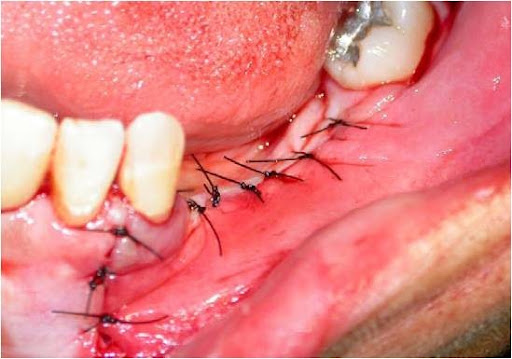

A manobra cirúrgica conclui-se com a sutura, tomando-se o cuidado de ocluir perfeitamente toda a loja cirúrgica e os implantes (Fig. 13).

Fig. 13 – A sutura realizada ocluindo-se perfeitamente toda a cirurgia.